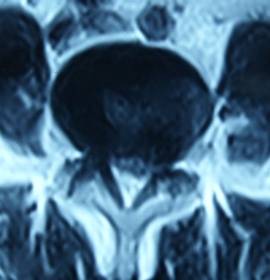

2. 患者董某,女,70岁,因“腰部疼痛并右下肢疼痛、麻木1年余,加重10天”入院。入院前曾多次行针灸、理疗、骶管封闭等治疗,经治疗后病情复发。入院见患者腰痛并右下肢疼痛,双足麻木,间歇性跛行,跛行距离约50米。查:直腿抬高试验右30°阳性,右踇背伸肌力、腓骨长短肌肌力Ⅲ级,双小腿外侧、足背皮肤感觉减退,右侧为甚。入院后诊断为腰椎间盘突出症。患者既往患高血压、冠心病、慢性胆囊炎、胆结石病史,形体肥胖。入院后完善检查,明确诊断,请相关科室会诊后认为手术风险大且患者形体肥胖,为手术增加难度,势必延长手术时间,增加手术风险。经科室讨论后行经皮椎间孔镜下髓核摘除,手术麻醉方式为局麻。入院后第三日手术,经椎间孔入路椎间孔镜下髓核摘除椎管扩大成形术。手术顺利,术中无出血,手术时间约1小时。术中可与患者交流。术后患者即可感右下肢无疼痛,第二天佩戴腰围下地活动后双下肢无不适。术后第三天出院,术后第三天复查腰椎MRI示突出髓核已摘除,神经根无受压。术后随访三月,患者目前病情恢复良好,无下肢疼痛。

术后第三天腰椎MRI